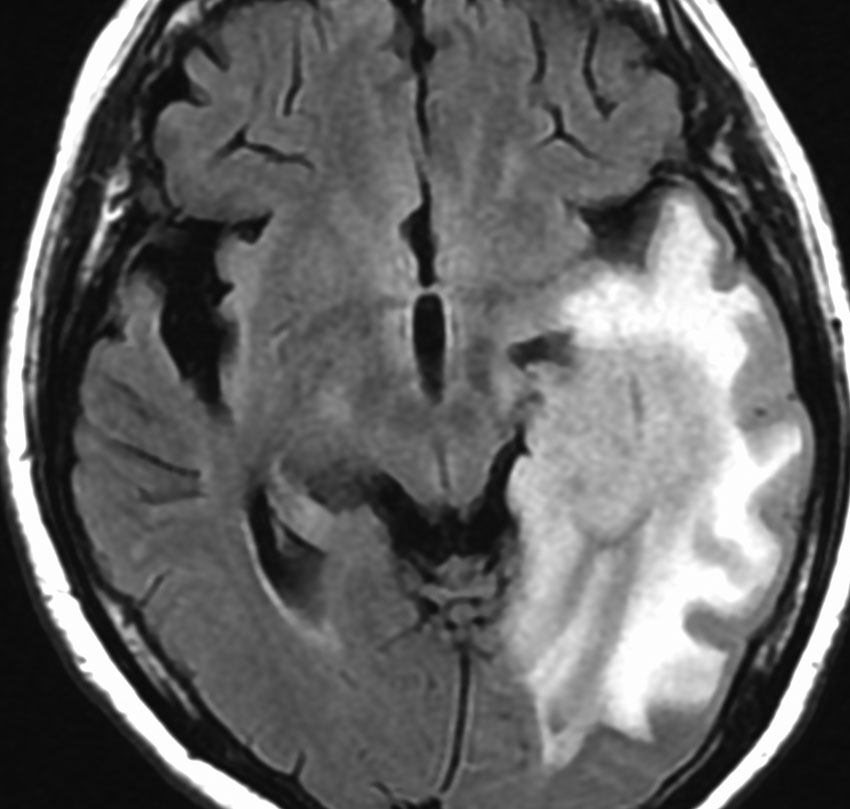

悪性転化 malignant transformation,膠芽腫への進展 progression

40代の患者さんです。夜間睡眠中の全般発作(症候性てんかん)で発症しました。フレア画像で左上前頭回に滲むような高信号領域(白い部分)がみられます。右側はガドリニウム増強MRIですが,全く増強されません。グレード2か3の星細胞腫あるいは乏突起膠腫を疑います。白く滲むような領域はよく見るとかなり広範囲に広がっています。

画像上では全摘出 gross total removalできて,病理診断は,退形成性乏突起星細胞腫 anaplastic oligoastrocytomaでした。IDH変異あり,1p/19q欠失なしです。現在の診断なら,退形成性星細胞腫 グレード3です。

手術後に54グレイの広範囲な局所放射線治療とテモゾロマイド化学療法を行いました。左の画像は放射線治療計画の時の線量分布図です。

5年後にいきなり激しい再発を生じました。再発部位は,放射線照射野外 out-of-fieldの前頭部帯状回でした。手術前に急速に増大して,画像所見も初回と全く違いました。摘出後の病理は,IDH1/2 wild type, 1p/19q intact, ATRX negative, MGMT met negative, MIB-1 40%という典型的な膠芽腫の所見でした。

この例とは異なって,退形成性星細胞腫の再発時には,IDH mutantのままの方が多いです。もしかすると先行した放射線誘発膠芽腫かもしれません。